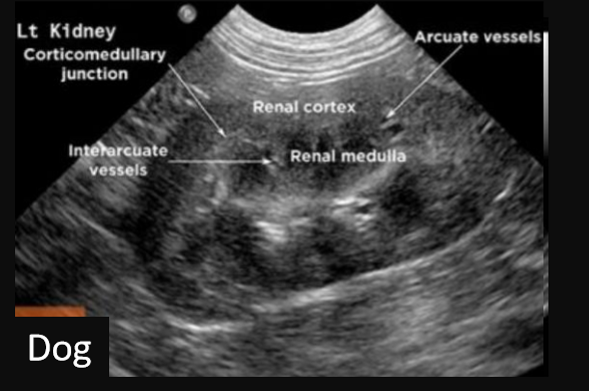

Q

Label this frontal/dorsal view kidney ultrasound